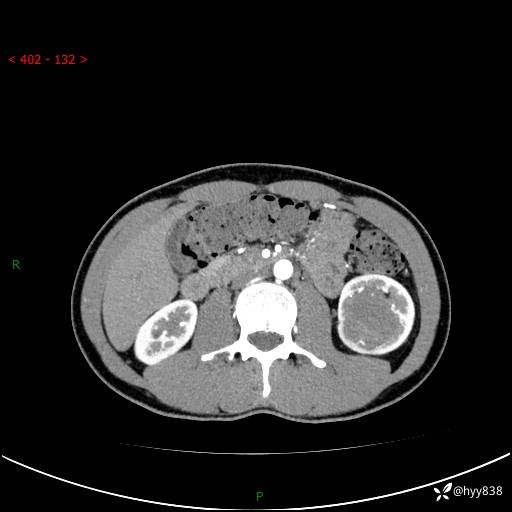

现病史:患者昨日中午进食后出现明显腹痛,腹泻,在我院急诊科行补液及对症治疗,双肾输尿管彩超提示左肾占位(5.2*4.3cm),平素无明显腰痛,无再发肉眼血尿等情况,现为求处理左肾占位,遂来我院,门诊以左肾占位收治入院。 患者起病以来,精神、食欲、睡眠尚可,大便可,小便如上,体力体重无明显下降。

双肾CT平扫+增强(三期)